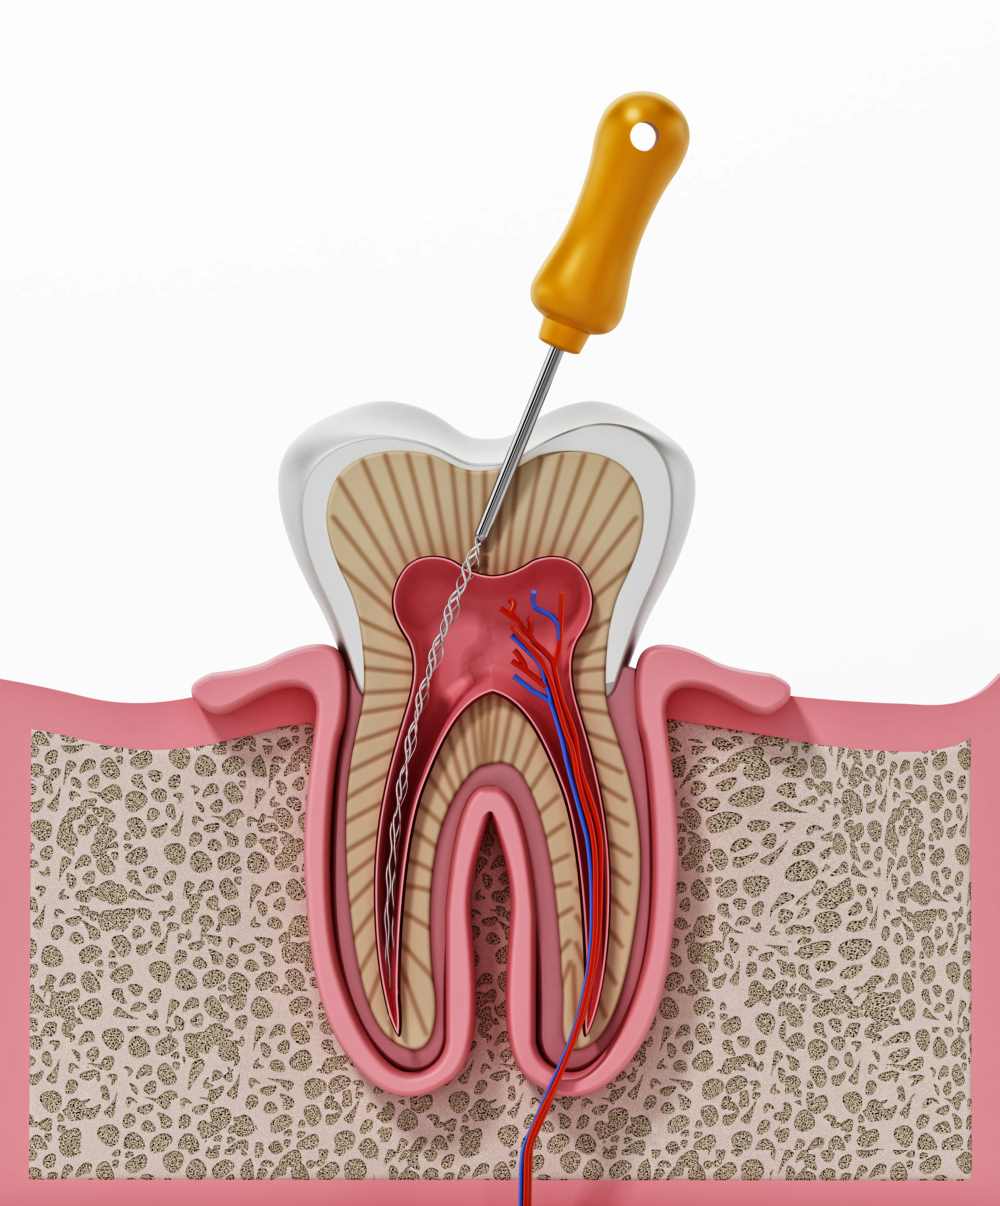

Sok esetben a fog olyan nagy mértékben károsodik – például az íny széléig letörik fogszuvasodás, fogelhalás vagy baleset következtében -, hogy arra már nem lehet koronát vagy hidat építeni, mivel nincsen elegendő foganyag. Ilyenkor jó megoldás lehet a csapos fogpótlás, mellyel a fog visszaállítható eredeti esztétikai állapotába.

A csapos fogpótlás menete

- A csapos fogpótlást minden esetben valamilyen képalkotó vizsgálat, például panoráma röntgen készítése előzi meg, hogy a szakorvos fel tudja mérni a fog és a gyökerek állapotát, megállapítsa, hogy nincs-e gyulladás.

- A csapos fog felépítéséhez előzetes gyökérkezelés szükséges. Amennyiben már gyökértömött a fog, a szakember ellenőrzi, hogy hibátlan-e a tömés. Amennyiben szükséges, cseréli.

- A kezelés során a gyökérbe beépítésre kerül egy csap, ami a kialakítandó fogcsonk alapjául szolgál. Egy része a gyökérben rögzül, míg másik fele a szájüregben van és fogcsonkot képez, amire aztán korona vagy híd készül.